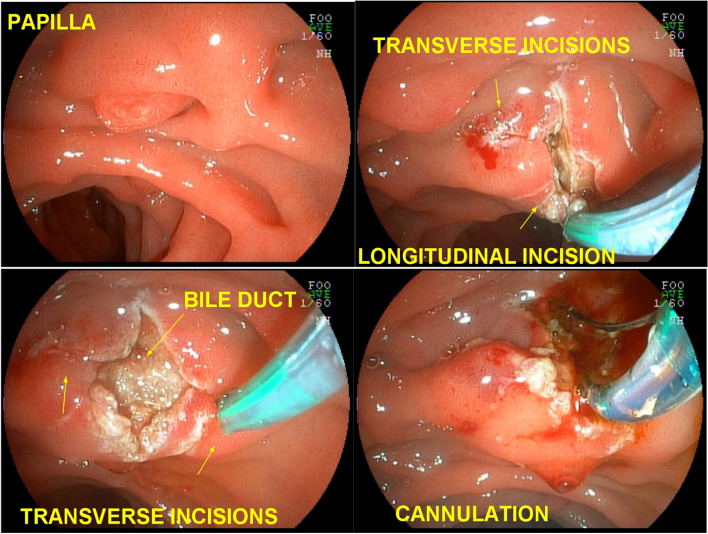

After identification and “palpation” with the tip of the fistulotome of the lateral limits of the papilla and exposure of the infundibulum, a wide, shallow incision only of the papillary mucosa was iniciated and, purely cut, with the fistulotome needle adjusted to approximately 2 mm, from top to bottom, just below the transverse crease, avoiding opening the region of the common channel. With the needle-knife, the needle was retracted, and the mucosal edges were pushed aside to expose the submucosa. Lateral incisions were made to expand the exposure and then superficial incisions were made to open the submucosa and, dissect thin layers one at a time, interspersed by blunt dissection with the tip of the needle-knife retracted; these steps were followed by identification of vessels, hemostasis and exposure of the sphincter muscle of the distal common bile duct. If bleeding occured, washing was performed with pressurized water through the fistulotome catheter itself or through the working channel of the duodenoscope, the bleeding point was identified and captured with hot biopsy forceps and sealed by seizure, rapid hemostasis was achieved by coagulation, and underlying thermal tissue damage was avoided. At this stage, transversal accessory incisions were made to remove the mucosa over the papilla and improve exposure (Fig. 2).

Subsequently, sectioning of the muscle fibers and of the common bile duct mucosa was performed, with bile outflow in most cases. Once the common bile duct mucosa was identified, the guide wire was introduced, confirmed by radioscopy and bile duct contrast (Fig. 3) (video 1).